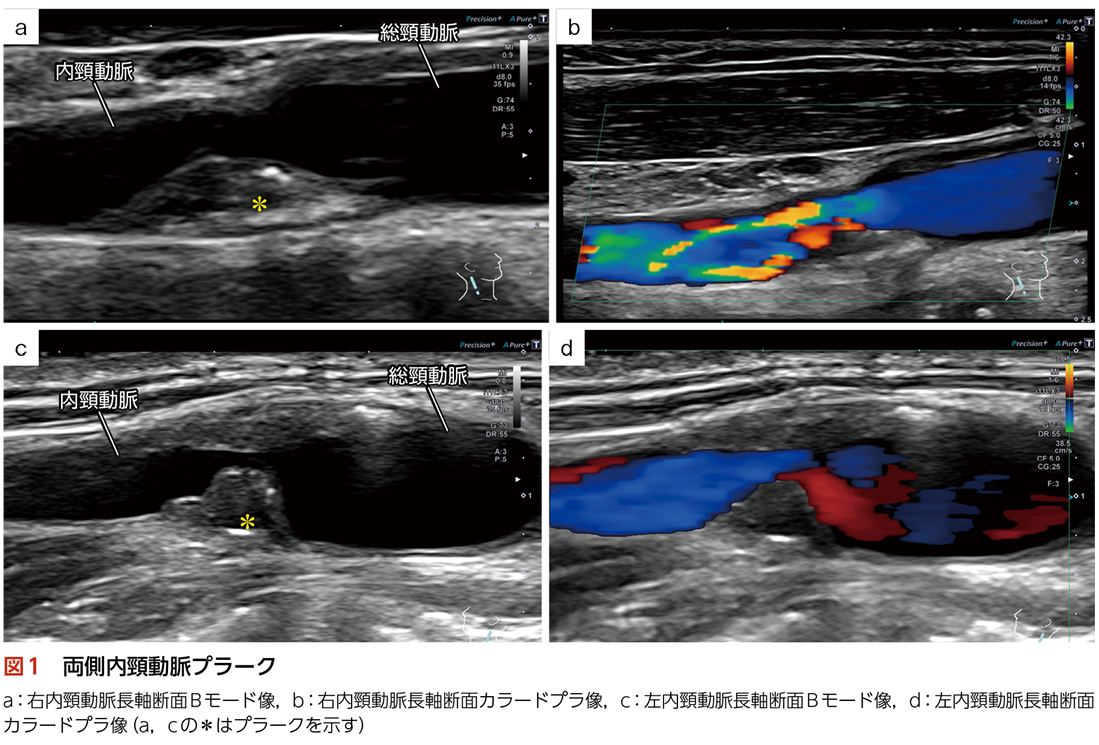

◆現病歴:右内頸動脈狭窄

◆検査目的:右内頸動脈狭窄が進行したため,経皮的内頸動脈ステント留置術の術前評価を目的として検査実施